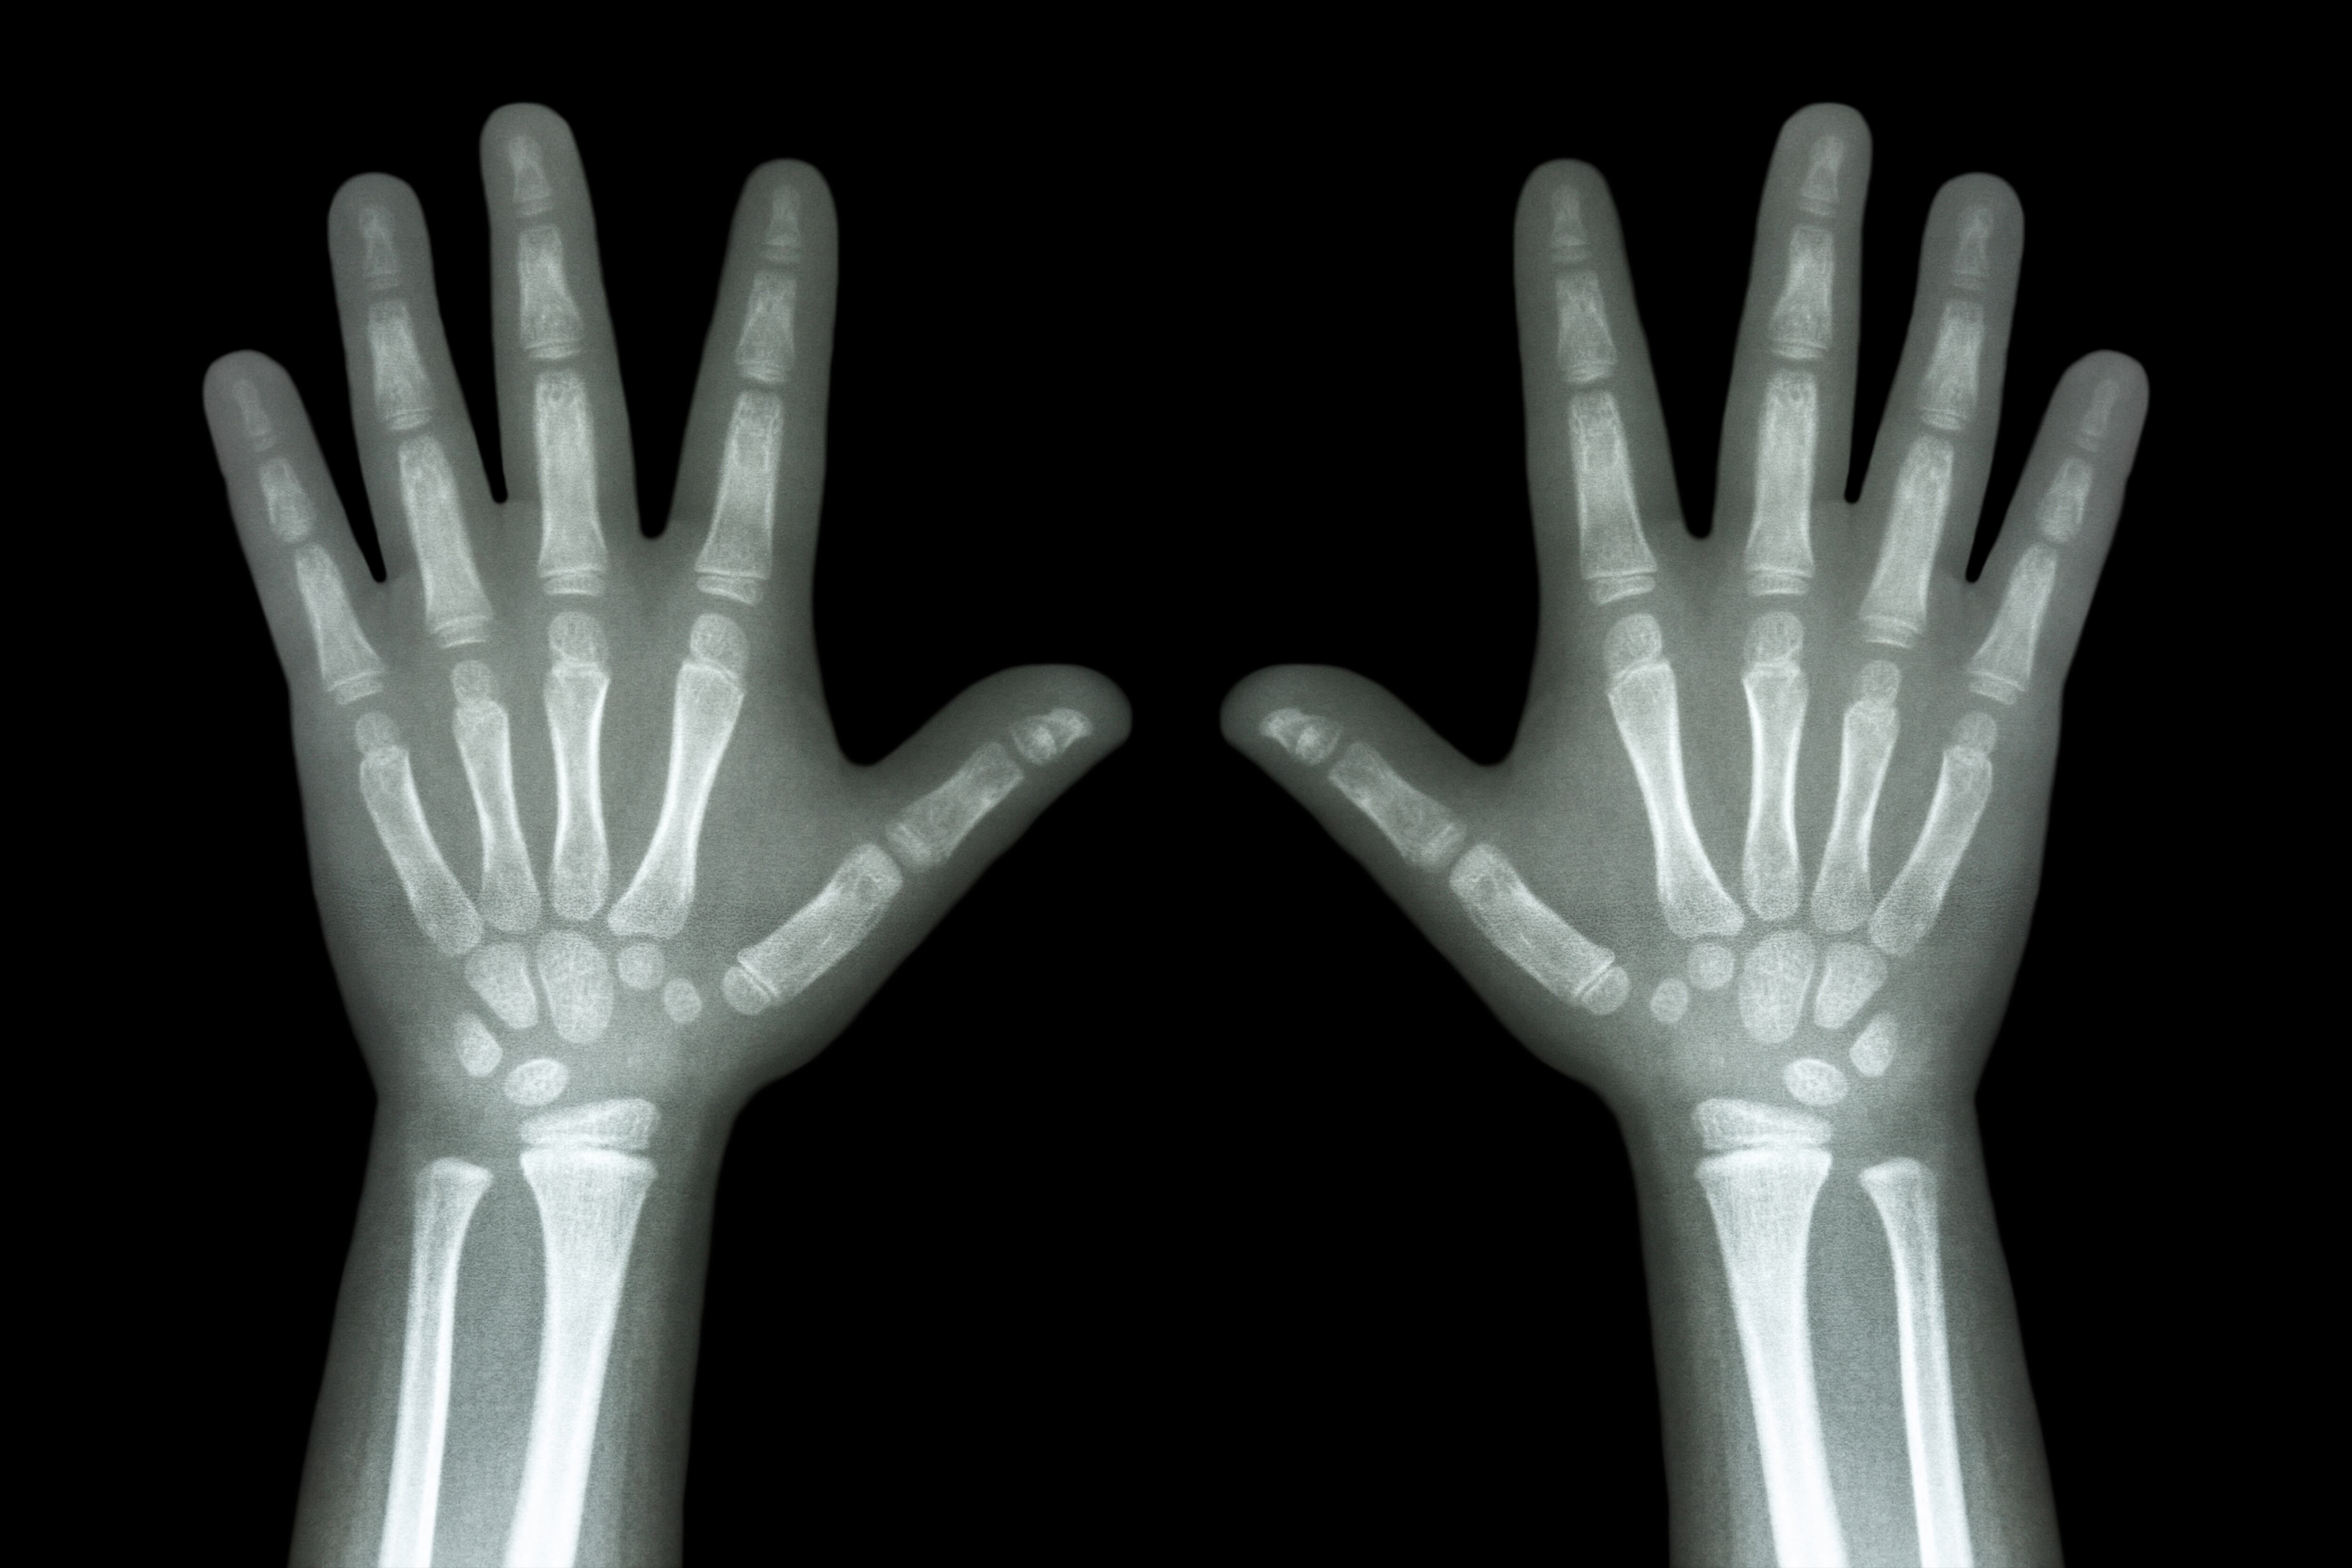

“Irrecuperables”. Esta es la situación de miles de radiografías y tomografías de pacientes a las que el Hospital Nacional de Niños no tiene acceso desde marzo, por una falla en el disco duro.

Esto implica la pérdida de información clave para medir la evolución de los padecimientos de cientos o miles de menores, o bien, que si alguno requiere recibir atención fuera del país, no es posible entregarle el expediente completo.